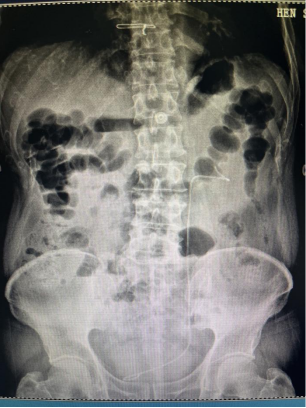

0007.png

术后复查泌尿系平片显示无结石残留、支架管位置正常